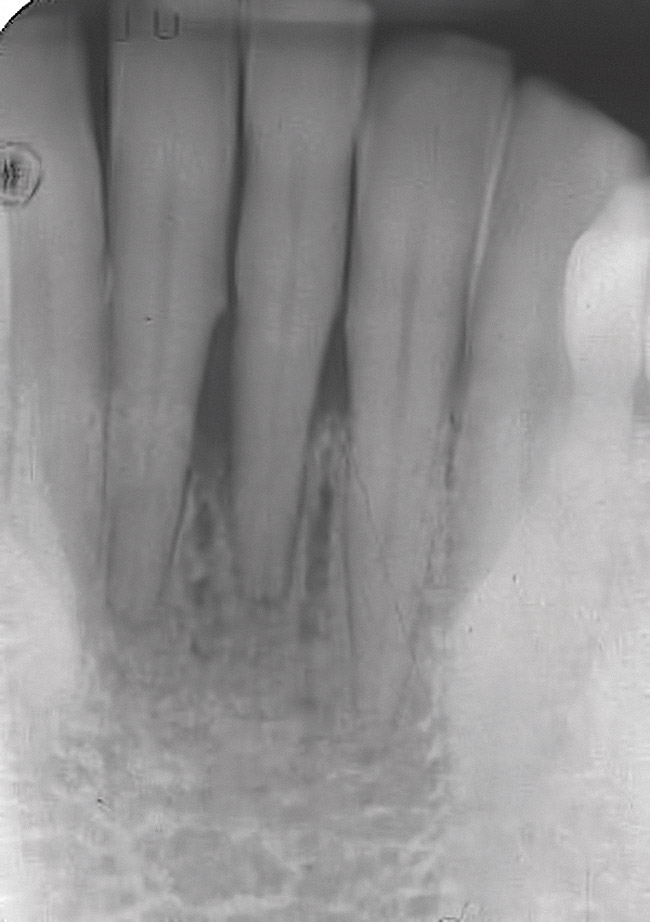

A 53-year-old man presented with localized advanced periodontal disease of the mandibular incisors. Teeth Nos. 23 to 26 exhibited class II mobility because of advanced bone loss (Figure 1). The teeth had migrated out of position over the years, and a diastema had developed between teeth Nos. 24 and 25 (Figure 2). The patient complained about the poor esthetic appearance of these teeth, and he was able to perceive their loss of strength on function as a result of their mobility.

Figure 2  The preoperative radiograph shows healthy cuspids and advanced periodontal disease on the four mandibular incisors.

Figure 2